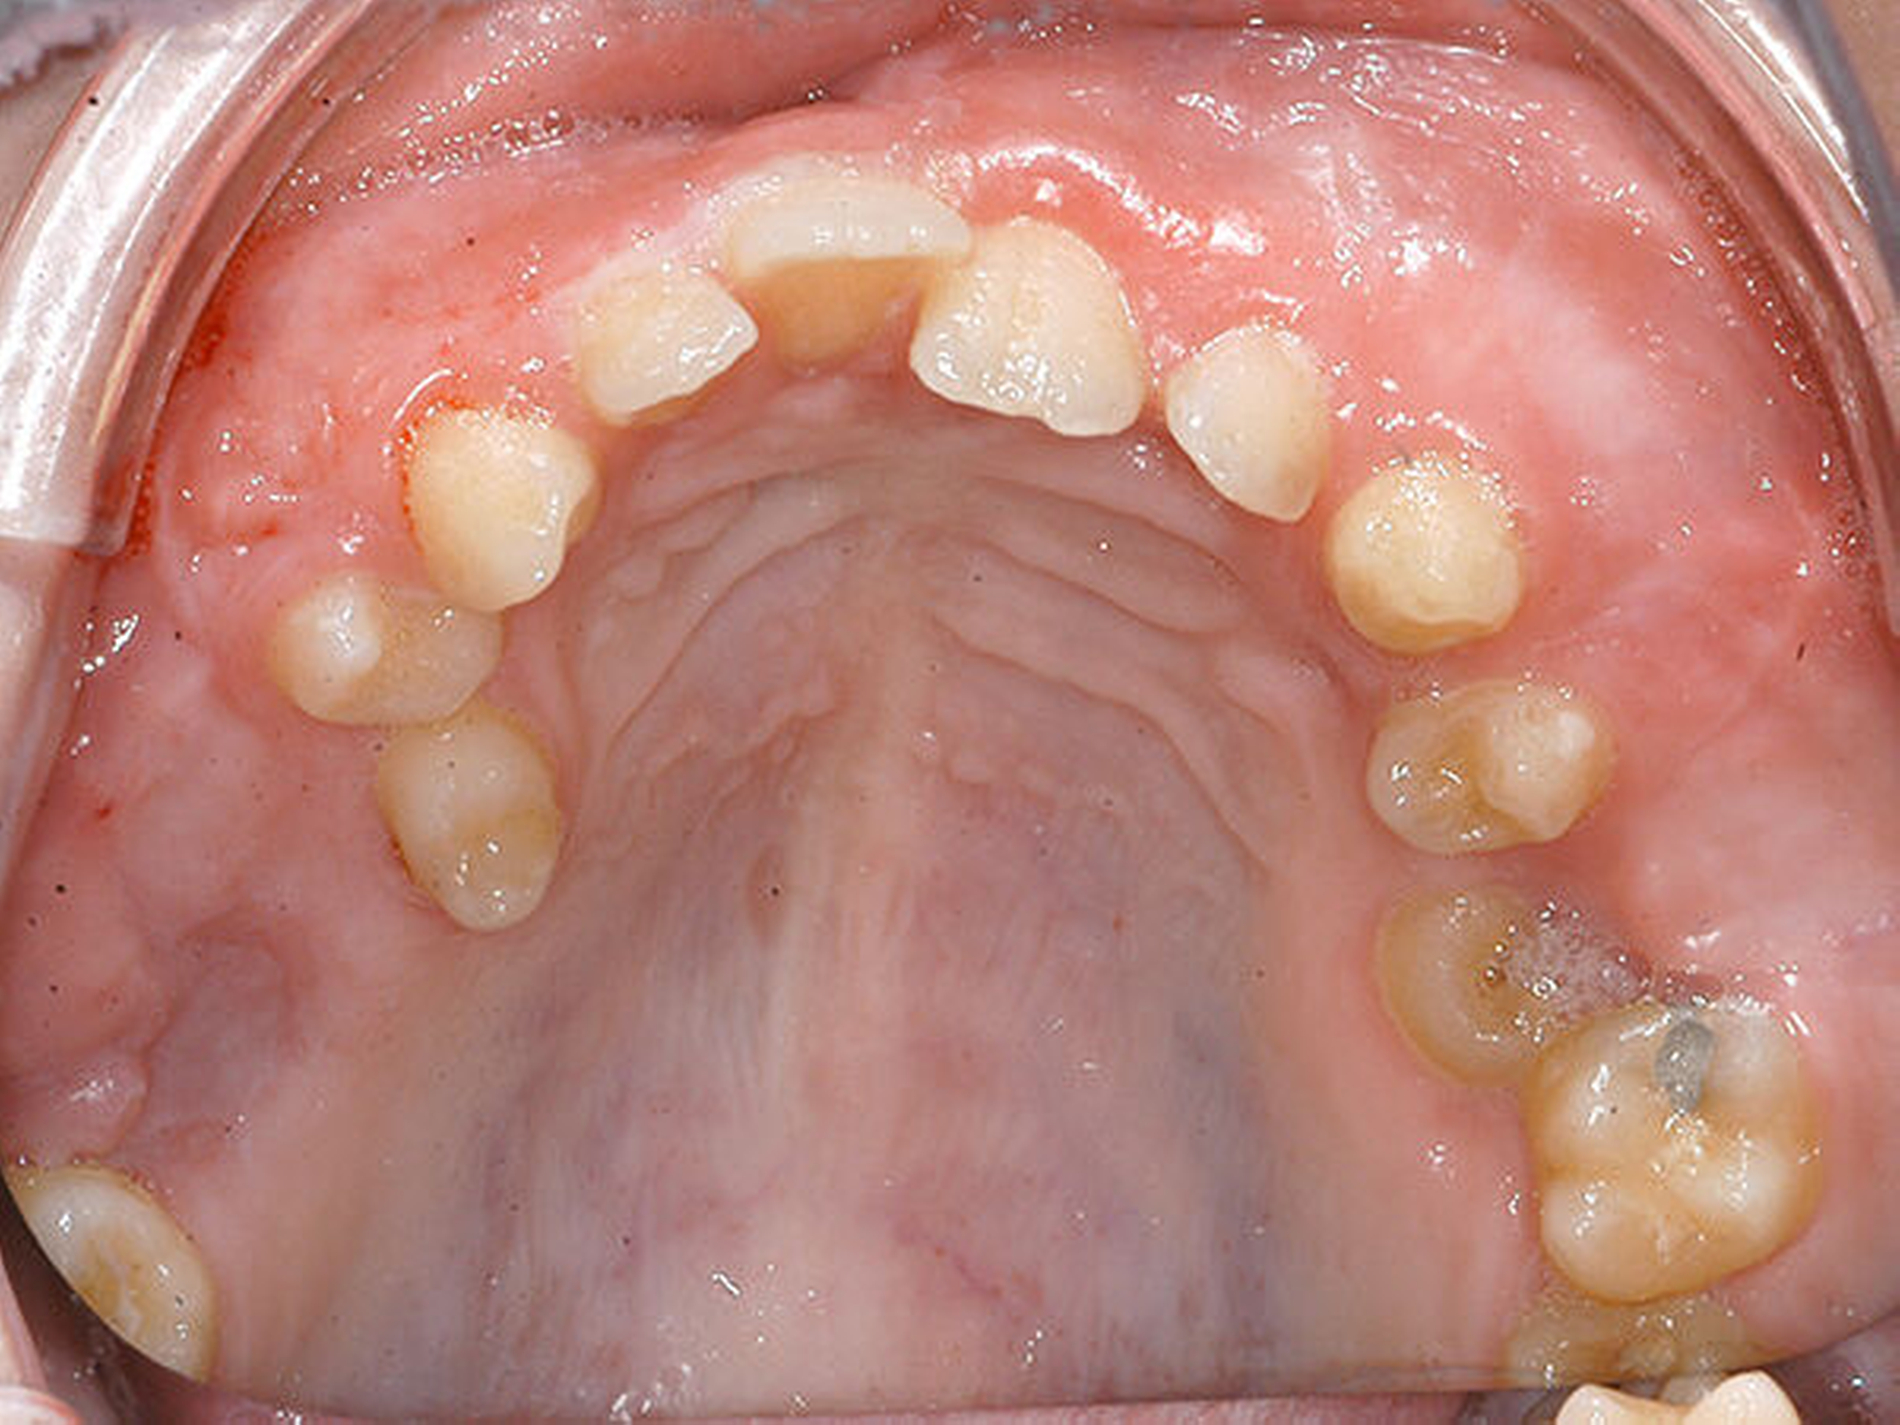

Die Entfernung des Zahns 16 erfolgte drei Monate später unter denselben Bedingungen. Etwa einen Monat nach Entfernung der Nähte zeigte sich eine unauffällige Wundheilung (Abbildung 4).